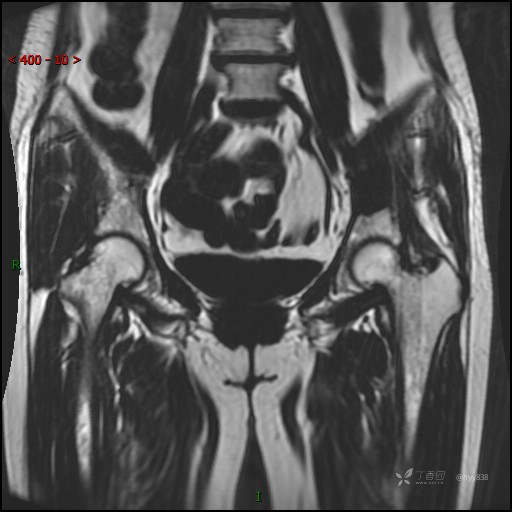

MRI T1WI+T2WI axi

Cor T1WI T2WI -fs